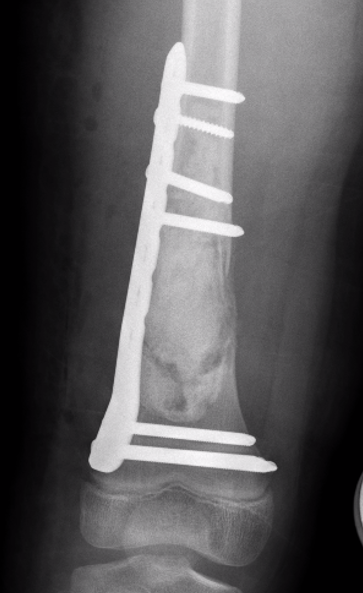

ORIF and bone graft

Indication

- fracture

- weight bearing bone

ORIF + fibular strut allograft

Jamshidi et al Int Orthop 2018

- 14 cases humerus UBC

- treated with locking plate + fibular allograft

- complete healing in 10, partial healing in 4